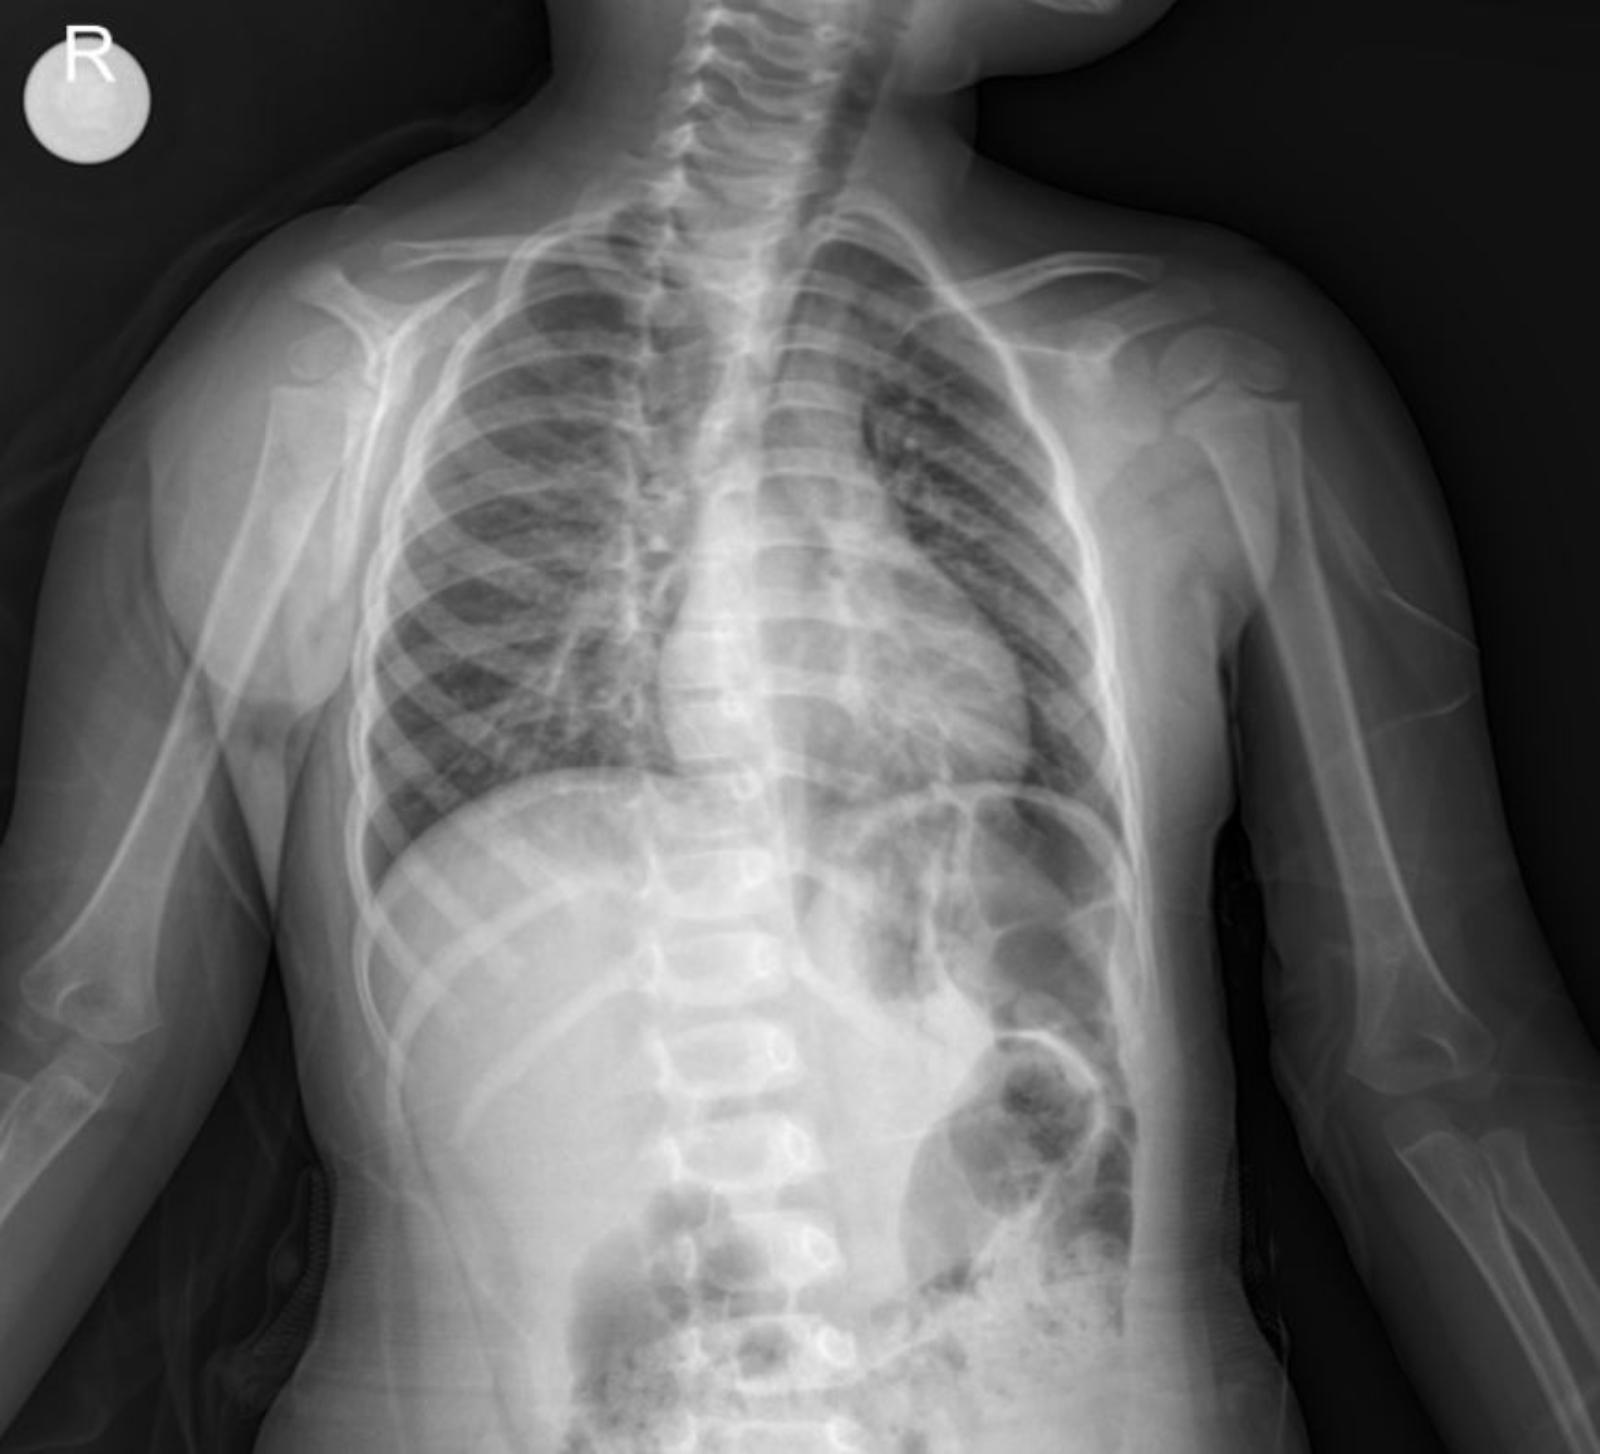

Radiological Findings: Chest X-ray

The provided anterior-posterior (AP) chest X-ray of the child reveals several significant findings:

- Lungs: The lung fields show evidence of peribronchial thickening and increased interstitial markings, consistent with an inflammatory process. Importantly, there is prominent paracardial infiltration, particularly noted around the left cardiac border. This suggests areas of consolidation or inflammation in the lung parenchyma adjacent to the heart, which is a common finding in bronchopneumonia.

- Heart: The cardiac silhouette appears within normal limits for size and contour for a pediatric patient, despite the adjacent infiltration.

- Diaphragm: The diaphragmatic contours are generally well-defined, with no evidence of significant pleural effusions.

- Bony Thorax: The ribs and clavicles appear intact, with no obvious fractures or deformities. The skeletal structures are appropriate for the child’s age.

- Trachea: The trachea appears patent and centrally located.

Considering the clinical history of worsening respiratory symptoms, fever, and hypoxemia, coupled with the X-ray findings of diffuse inflammatory changes and distinct paracardial infiltration, the diagnosis of bronchopneumonia is well supported.

This case effectively demonstrates how a combination of detailed clinical history, physical examination findings, and radiological evidence from a chest X-ray leads to the diagnosis and appropriate management of pediatric bronchopneumonia with paracardial infiltration. The presence of paracardial infiltration on the X-ray further characterizes the extent of the inflammatory process.